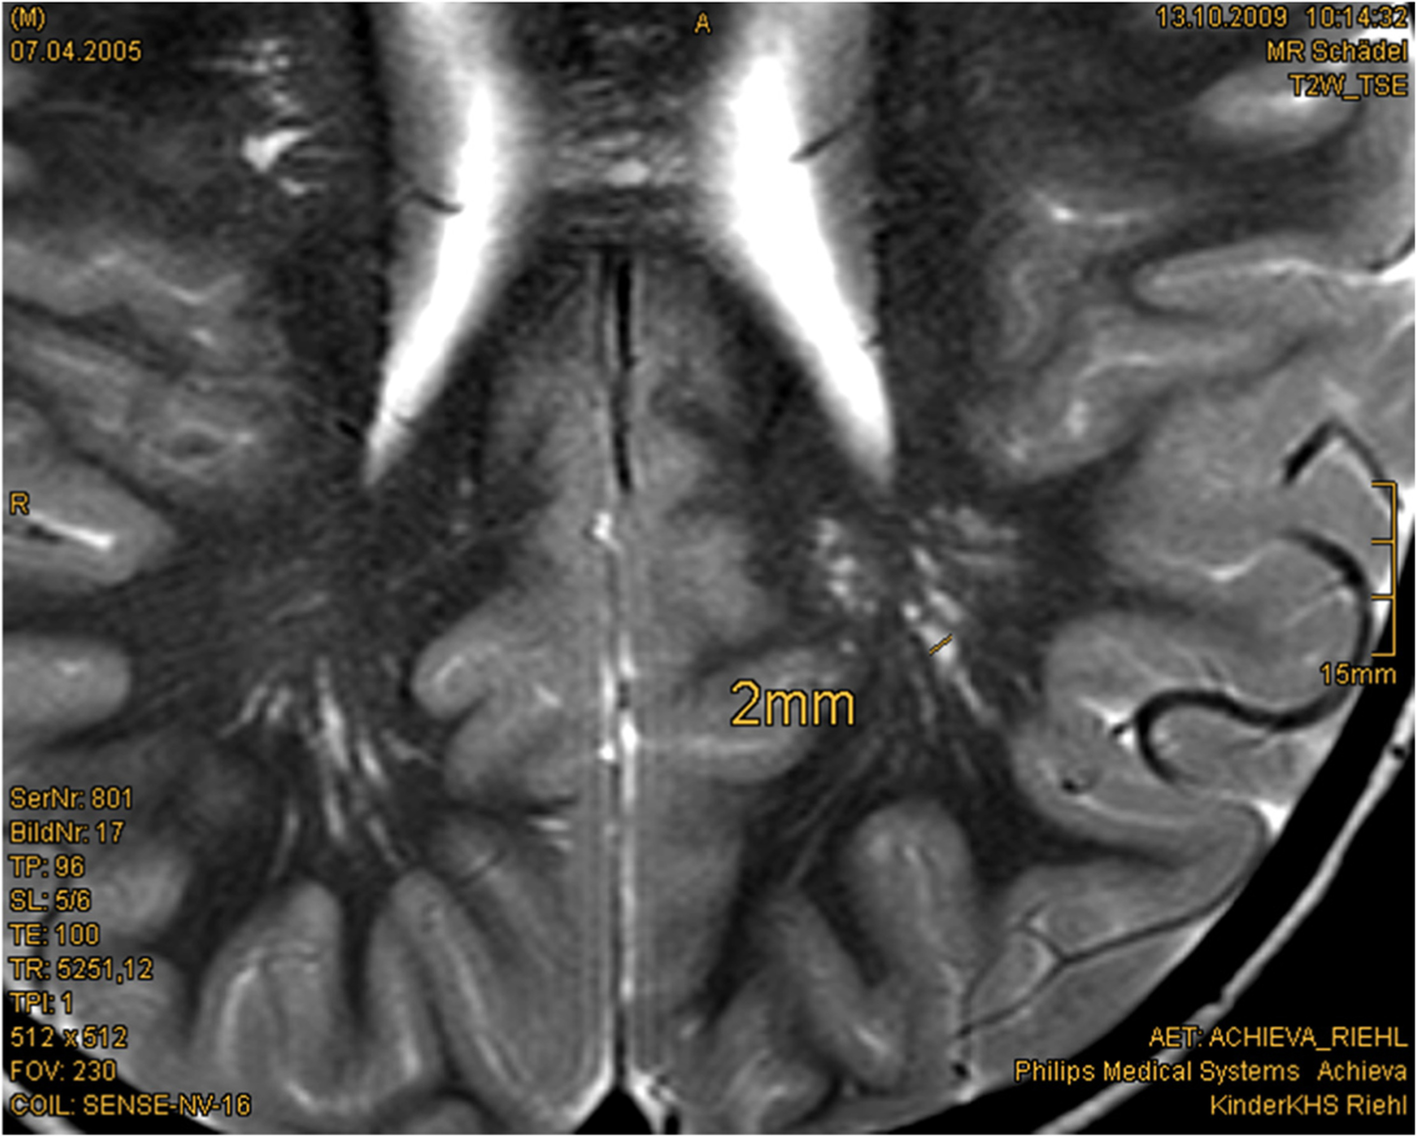

Most children with PHTS receive a cerebral MRI as part of the diagnostic workup of macrocephaly. A high percentage shows enlarged perivascular spaces (EPVS) and white matter abnormalities. Therefore, detecting these abnormalities in cerebral magnetic resonance imaging (cMRI) might also help in establishing an earlier diagnosis in PHTS patients [20] (Fig. 1). In childhood, psychomotor assessment and, if necessary, further neurological diagnostic and treatment play a central role in the management of patients with PHTS. Muscle hypotonia might be treated with physiotherapy or supporting medical devices. In case of severe neurological symptoms or recurrent headaches, a cerebral MRI should be performed. In adults, cerebellar dysplastic gangliocytoma (Lhermitte–Duclos syndrome) should be excluded. Vascular malformations could be located anywhere and cause diverse symptoms. To the best of our knowledge, there is no proved genotype–phenotype correlation for the extent of neurological symptoms.

Fig. 1

Enlarged perivascular spaced (EPVS) in cerebral MRI: 4.5-year-old boy, T2w-image, EPVS 2 mm diameter [Courtesy Kinderkrankenhaus Kliniken der Stadt Köln]